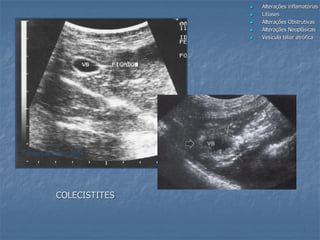

Colecistite

 Aspecto variável:

- espessamento da parede

- presença ou não de lama

- presença ou não de cálculos

- Sensibilidade dolorosa aumentada durante

a varredura US na região - sinal de

Murphy (Ralls et al, 1982)

COLECISTITES

Fonte: Carvalho, 2004